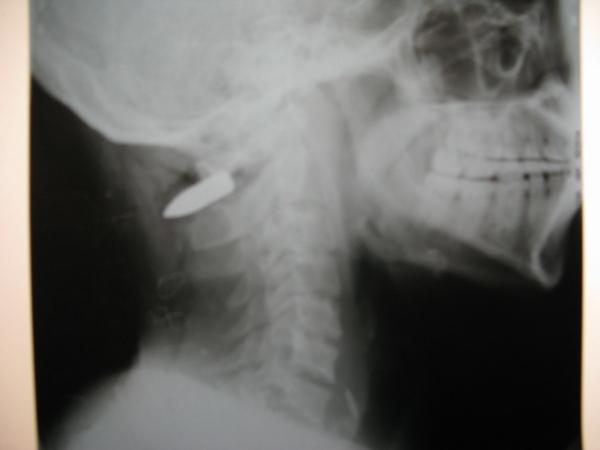

Depuis début avril, la reprise du confit a conduit à d’importants déplacements de populations et a provoqué un accroissement de la morbi-mortalité de certaines maladies ainsi qu’un nombre important de blessures par balles.

"Dans les dernières semaines, nous avons vu une augmentation des cas de malnutrition, des infections respiratoires et des infections sexuellement transmissibles (IST). Nous avons également pris en charge plus d’une vingtaine de patients directement blessés par les combats", rapporte Corry Kik, coordinateur médical de MSF au Nord-Kivu.

D'autres patients ont été directement blessés par la violence armée, comme Momo qui a été transféré dans un hôpital soutenu par MSF, avec cinq autres patients. "J'ai décidé de quitter ma maison et de voyager à Goma pour voir ma famille et prendre soin de quelques affaires. Je suis partie en taxi avec 20 autres passagers à 7:00 heures du matin. Dix minutes après notre départ, j'ai entendu une série de coups de sifflet, puis 30 secondes plus tard, les tirs ont commencé. J'ai été frappé par deux balles à la jambe droite et une à la gauche. Les quatre hommes masqués n'ont même pas essayé d'arrêter le véhicule. La population est la première victime de ces affrontements."